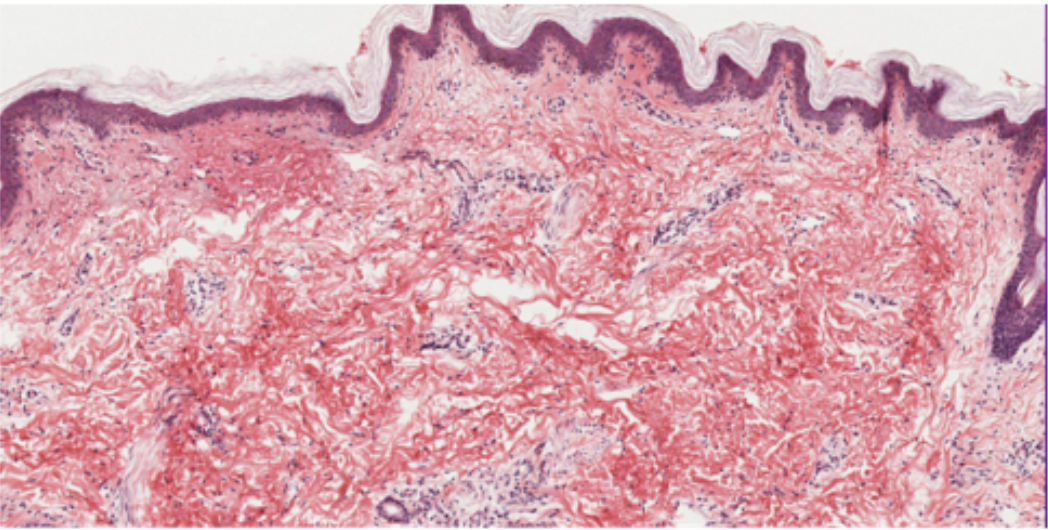

blue

stratum corneum

red

stratum lucidium

green

stratum granulosum

pink

stratum spinosum